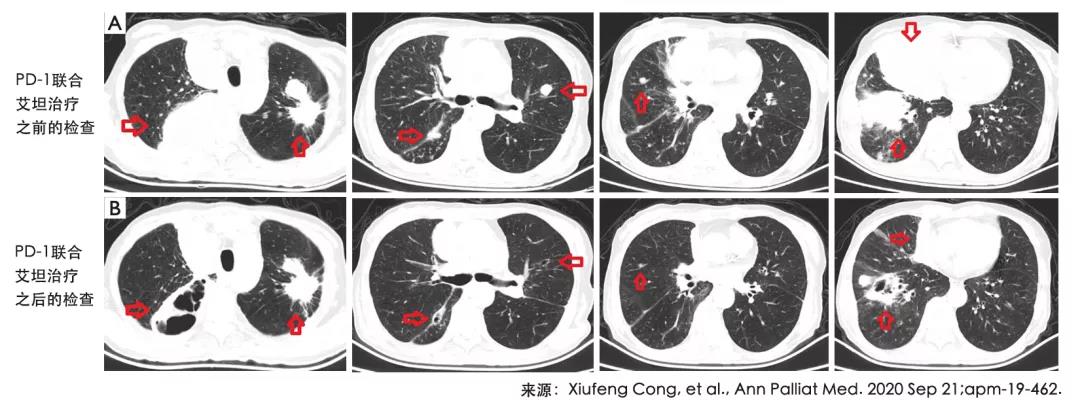

一个月以后,胸部CT的扫描发现双肺病变明显减少,并且出现坏死的迹象。但是肝部病灶没有发生变化。但患者体感不错,呼吸问题明显减少。ECOG体能评分也从3变成了1。

目前患者仍在接受治疗,而且没有发生与治疗相关的不良反应。直到2020年3月,患者肺部病变仍处于部分缓解状态,且生活质量良好。